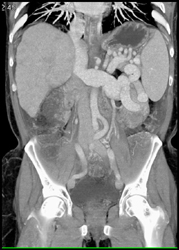

Cirrhosis With Varices